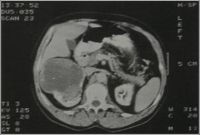

Nierentumore werden in erster Linie durch die Ultraschalluntersuchung diagnostiziert. Um bösartige Tumoren von gutartigen Prozessen der Niere zu unterscheiden, wird heutzutage eine Computertomographie (CT) durchgeführt. Mit dieser Untersuchung gelingt es Größe und Ausdehnung des Tumors in der Niere zu bestimmen. Des weiteren kann bei dieser Untersuchung ein möglicher Befall von Nachbarorganen und Lymphknoten erkannt werden.